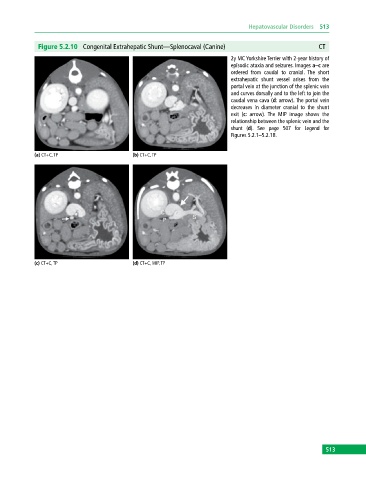

Figure 5.2.10 Congenital Extrahepatic Shunt—Splenocaval (Canine) CT

2y MC Yorkshire Terrier with 2‐year history of

episodic ataxia and seizures. Images a–c are

ordered from caudal to cranial. The short

extrahepatic shunt vessel arises from the

portal vein at the junction of the splenic vein

and curves dorsally and to the left to join the

caudal vena cava (d: arrow). The portal vein

decreases in diameter cranial to the shunt

exit (c: arrow). The MIP image shows the

relationship between the splenic vein and the

shunt (d). See page 507 for Legend for

Figures 5.2.1–5.2.18.

(a) CT+C, TP (b) CT+C, TP

(c) CT+C, TP (d) CT+C, MIP, TP